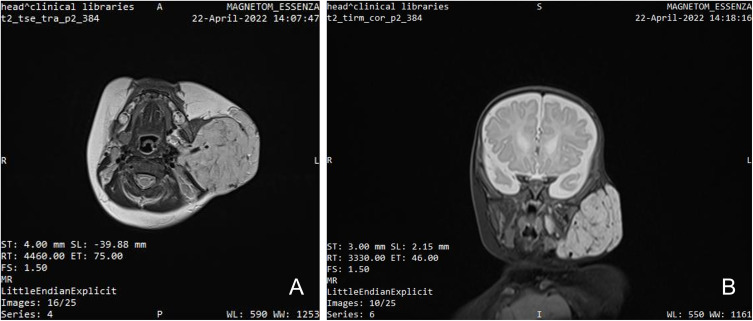

Case presentation: A two-month-old girl presented with a large unilateral parotid hemangioma, first noted on the 15th day of life, which had been rapidly increasing in size. Oral propranolol was initially prescribed, but treatment was not started by the parents, and the patient was lost to follow-up. At 3.5 months of age, the patient underwent an unplanned cosmetic surgical excision at a rural hospital, which resulted in facial nerve paresis and functional facial asymmetry. She re-presented at 7 months with a markedly enlarged lesion. Propranolol (3 mg/kg/day) was reinitiated; however, despite dose escalation, the hemangioma remained unresponsive. Systemic corticosteroids (prednisolone, 1-3 mg/kg/day) at 8 months were added, but the lesion continued to progress. At 9 months of age, metronomic chemotherapy with vinblastine (1 mg/m² IV every 3 days) and cyclophosphamide (50 mg/m² orally for 10 days) was introduced under clinical supervision. This combination resulted in significant tumor regression, as confirmed by serial imaging and clinical examination.